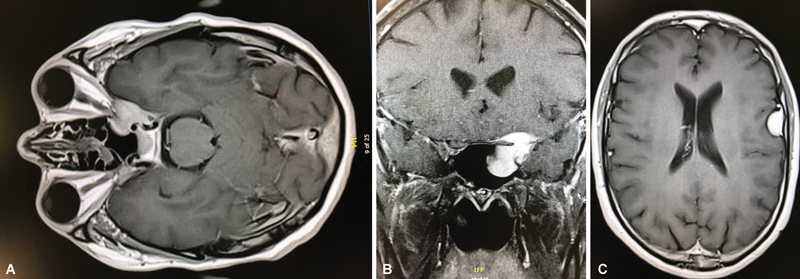

Anterior clinoid process metastases are rare. We present an unusual case of anterior clinoid process metastasis with sudden deterioration of visual function requiring emergency optic nerve decompression, resulting in recovery of visual function. The patient was a 41-year-old man with a diagnosis of leiomyosarcoma of the radius, operated on in 2014, with bone and lung metastases, who had been treated with chemotherapy and appeared to have stable disease at his last follow-up. Six years later, he developed a 1-month history of progressive unilateral loss of visual acuity and visual field defect (initially quadrantanopia that progressed to nasal hemianopia). Brain imaging showed a contrast-enhancing lesion affecting the left anterior clinoid process with extension to the cavernous sinus and sphenoid sinus, causing compression of the left optic nerve. Although the lesion could have suggested a meningioma given the location, in the context of the patient's oncological history, the diagnosis of metastasis was considered more likely. The patient was admitted to the hospital and, during the hospital stay, developed sudden left retro-orbital pain progressing to left amaurosis over approximately 8 hours. Urgent surgery was performed: a pterional craniotomy with partial tumor removal and optic nerve decompression with extradural anterior clinoidectomy. After surgery, the patient had an immediate but partial improvement in visual acuity and in the visual field defect. Metastasis to the anterior clinoid process is very uncommon, with only one case previously reported in the literature. In cases of visual impairment, symptoms may deteriorate rapidly to complete loss of vision, so urgent decompressive surgery of the optic pathway may be indicated to recover visual function, although recovery may be partial.